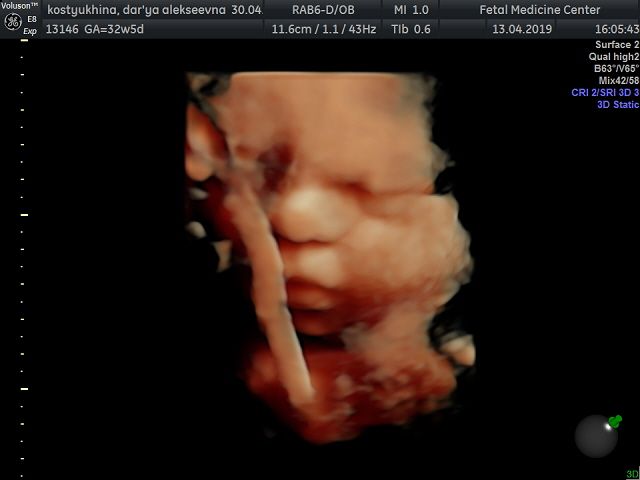

Вот и добралась до флешки))) Наш сыночек в цвете ? смотрю и не верю!!! Какое же чудо природы, да и техники фото через органы? еще 1,5 мес и состоится встреча всей жизни ? Вчера после скрининга зашли в кафе израильское, малыш ликует от этой пищи!!! С собой взяли паштет из тунца с кедровыми орешками и сушеной клюквой, села кушать и снова танцы ? блин даже от сладкого такого нет ? А что любят ваши малыши?)